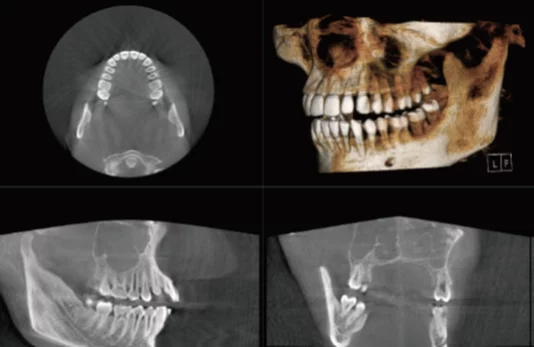

Third are the medium size FOV dental cone beam machines (e.g. 16 x 8). Below are examples of a 16 x 8 volume (3D reconstruction, axial and sagittal views):